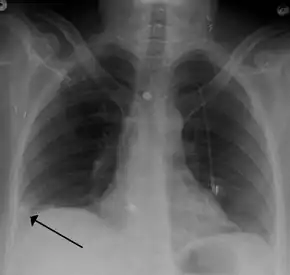

- Chest X-rays are often done on people with shortness of breath to help rule-out other causes, such as congestive heart failure and rib fracture. Chest X-rays in PE are rarely normal,[59] but usually lack signs that suggest the diagnosis of PE (for example, Westermark sign, Hampton's hump).